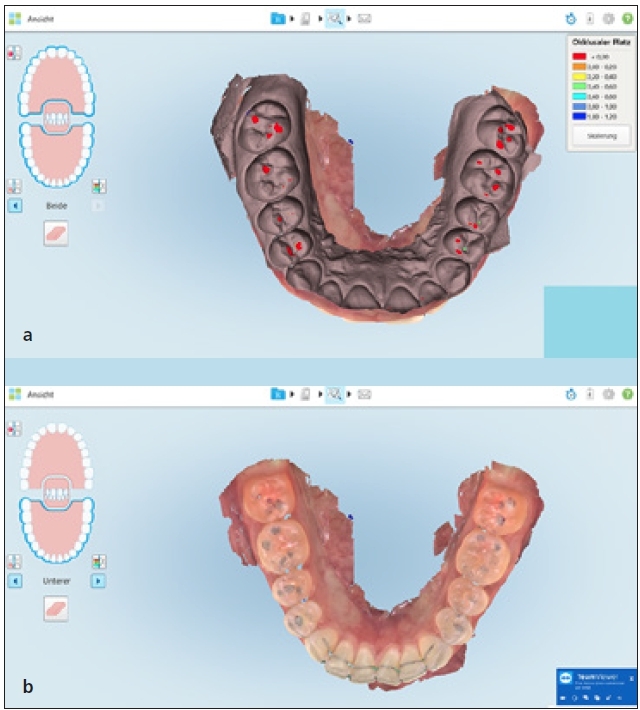

Die Genauigkeit

Der sicherlich entscheidende Faktor für jede Abformung ist die Genauigkeit. Diese ist heute sehr gut untersucht. Eine Studie der Deutschen Gesellschaft für digitale orale Abformung (DGDOA) aus dem Jahr 2016, die 29 Untersuchungen zur Genauigkeit unterschiedlicher intraoraler Scansysteme zusammengefasst hat, sowie eine weitere Untersuchung aus dem Jahr 2017 zum Vergleich unterschiedlicher Intraoralscanner zeigen, dass beinahe alle am Markt verfügbaren Scanner über eine ausreichende Genauigkeit zur Versorgung von einzelnen Restaurationen, aber auch im Gesamtkiefer verfügen. Scannerspezifisch gibt es hier gerade auf den Gesamtkiefer bezogen jedoch deutliche Unterschiede. Wichtig ist, wenn man sich mit Studien zur Genauigkeit befasst, auf die genaue Bezeichnung des getesteten Scanners und vor allem der genutzten Software zu achten. Viele Studien, die neu erscheinen, behandeln Scansysteme und Softwareentwicklungsstufen, die in dieser Form schon gar nicht mehr auf dem Markt sind. Zu einigen Scansystemen gibt es allerdings noch keinerlei wissenschaftliche Untersuchungen. Es ist deshalb wichtig, sich bei der Anschaffung eines Gerätes hier genauer zu informieren (Abb.2 a–d). Dr. Ingo Baresel

Auch die Sitzposition beim Scanvorgang bedingt das Handling des Scanners. Je nach bevorzugter Sitzposition sollte es möglich sein, in der Software des Intraoralscanners die Sitzposition vor oder hinter dem Patienten auszuwählen. Ein ausführlicher Test der Sitzposition beim Scan am Patienten ist hier dringend zu empfehlen (Abb. 3a und b).

Die Scanstrategie

Einer der größten Unterschiede zwischen Intraoralscannern findet sich in der Strategie, die Restbezahnung, Präparationen und die Bisssituation zu erfassen. So bestehen prinzipiell 3 Optionen: Die erste Option ist der Scan des gesamten Kiefers inklusive aller Präparationen. Die zweite Möglichkeit ist ein Scan des zu präparierenden Kiefers vor der Präparation. Nachdem diese erfolgt ist, werden die entsprechenden Zähne automatisch aus dem Erstscan gelöscht und es erfolgt ein Scan der präparierten Zähne, die dann in den Vorpräparationsscan eingerechnet werden. Die dritte Option ist ein Scan jedes einzelnen präparierten Zahnes; diese werden dann in einen Scan der Gesamtsituation automatisiert eingerechnet. Jede dieser Optionen hat individuelle Vorteile; deshalb sollte man bei der Entscheidung für den einen oder anderen Intraoralscanner seinen gewünschten Workflow zugrunde legen (Abb. 4 u 5). Dr. Ingo Baresel